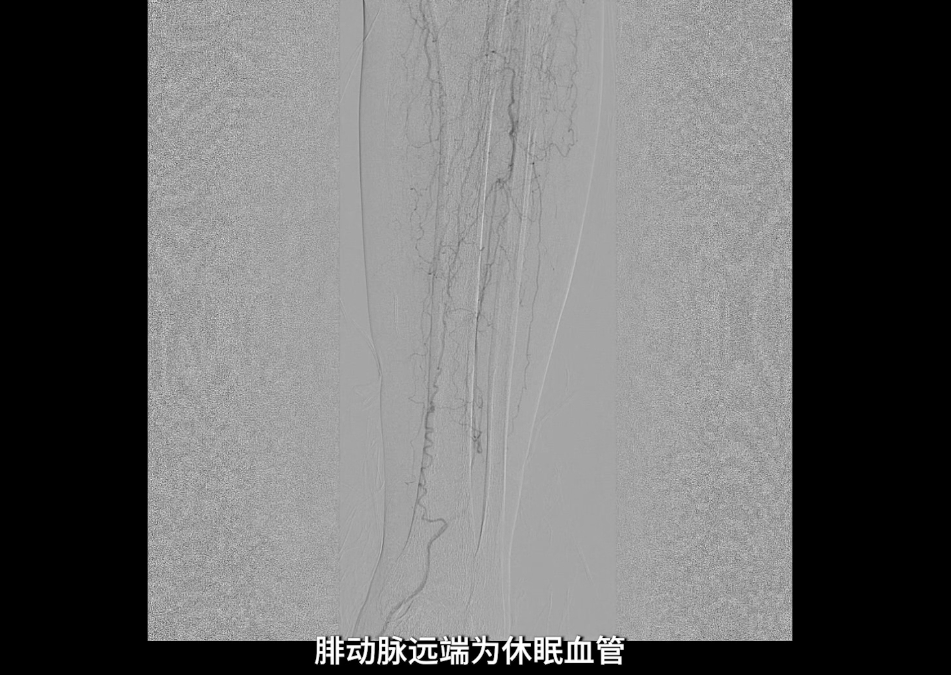

术中造影确认病变

左侧股浅动脉中上段明确长段狭窄并闭塞,病变长度约15cm,股浅动脉远段至腘动脉管腔通畅。

膝下动脉三支主干均闭塞,胫后动脉远端经侧支循环显影;腓动脉远端为“休眠血管”,通过与胫后动脉的交通支实现逆向显影。